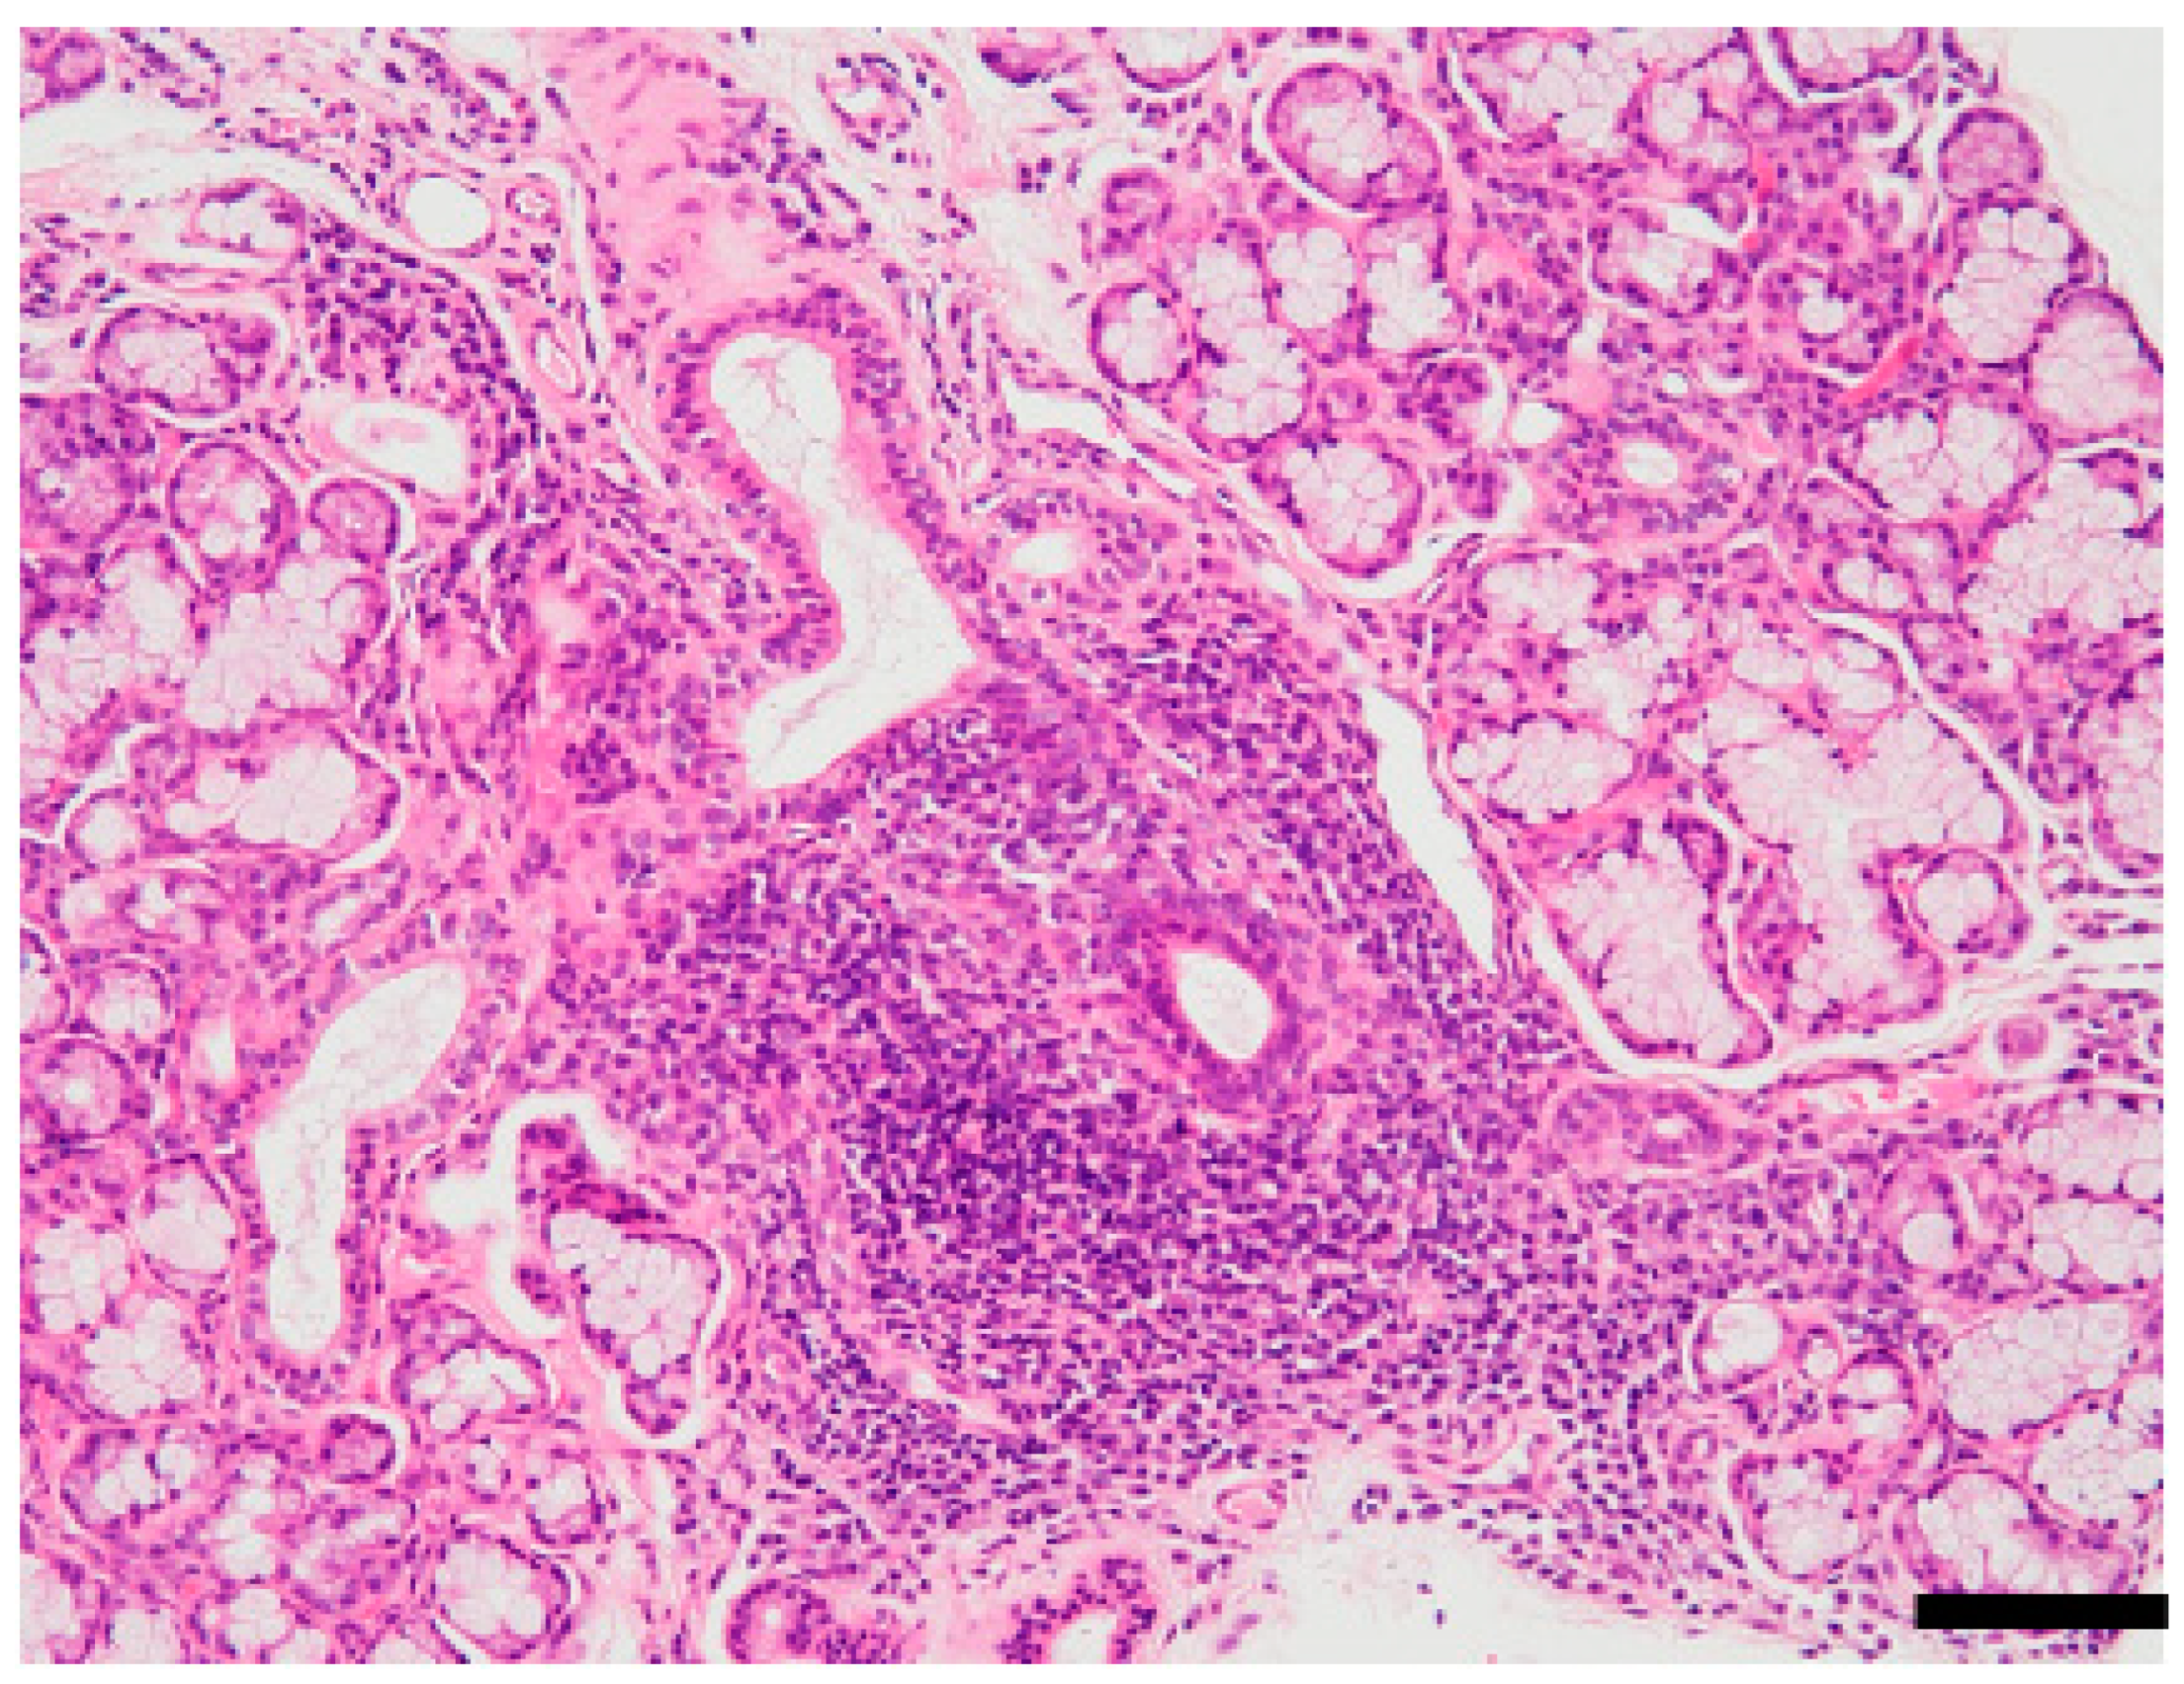

A variety of viruses, including EBV, HTLV, HSV, HBV, HCV, and CMV, have been reported to be associated with the development of SS [24,31], and infection with these viruses is known to be a clinical risk factor [1]. Pathogenesis of SS is very complex, as evidenced by multiple lesions observed in glandular and extra-glandular organs. A typical pathological feature of the salivary glands of patients with SS is a focal accumulation of lymphocytes around the salivary duct (Figure 1). The inflammatory lesions in the target organ are formed during a complicated process via the breakdown of central or peripheral immunological tolerance, affected by genetic and/or environmental factors, including viral infection [3].

Figure 1.

Focal lymphocytic sialadenitis of Sjögren’s syndrome (SS). Hematoxylin and eosin (HE)-stained section of minor salivary glands prepared from lip biopsy from a patient with SS. Notice the lymphocytic infiltration around the salivary ducts and the atrophy of acinar cells. Pathological diagnostic criteria of SS is ≥1 focus score or Greenspan grade ≥ 3 [32,33]. One focus refers to an aggregate of ≥50 mononuclear cells, including lymphocytes, histiocytes, and plasma cells around the ductal structure. Scale bar: 100 μm. The image is unpublished.